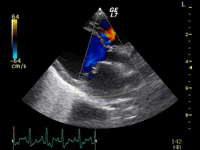

A:超音波カラードップラーでの僧帽弁逆流速度の測定

症例:【マルチーズ 12歳齢 去勢オス】

左側胸壁心尖部領域を最強点とするLevine 5/6の収縮期性心雑音が聴取された。

胸部レントゲン検査において重度の心拡大と肺水腫が認められた。超音波検査では、重度の僧帽弁閉鎖不全症、三尖弁閉鎖不全症、中程度の大動脈弁閉鎖不全症を合併していることが判明した。三尖弁逆流速度から肺高血圧症が示唆された。

ACE阻害薬、ピモベンダン、硝酸イソソルビド徐放剤、ベラプロストナトリウム、利尿剤としてフロセミドとスピロノラクトンを用いて治療を行った。